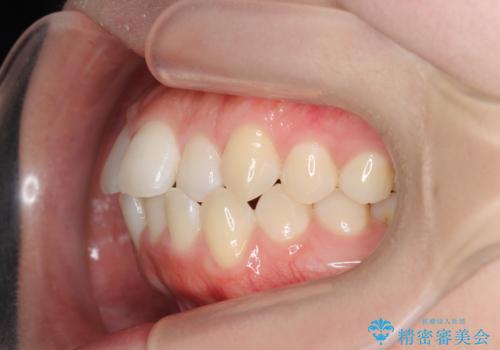

前歯のすれ違い インビザラインで行うマウスピース矯正

- 前歯のガタつき、でこぼこ、前後が逆になっている噛み合わせの改善を求めて来院されました。

治療の装置が目立たず歯ブラシのしやすいマウスピース矯正インビザラインでの治療を計画します。

20時間/日の装用時間をしっかりと守っていただき、きれいな歯並びを手に入れることができました。